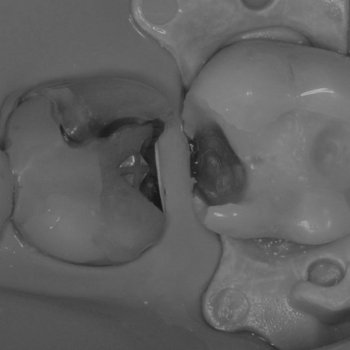

Пломба выпала — зуб спасли

Проблема: Пациент обратился с жалобой на выпадение пломбы из зуба.

Лечение и результат